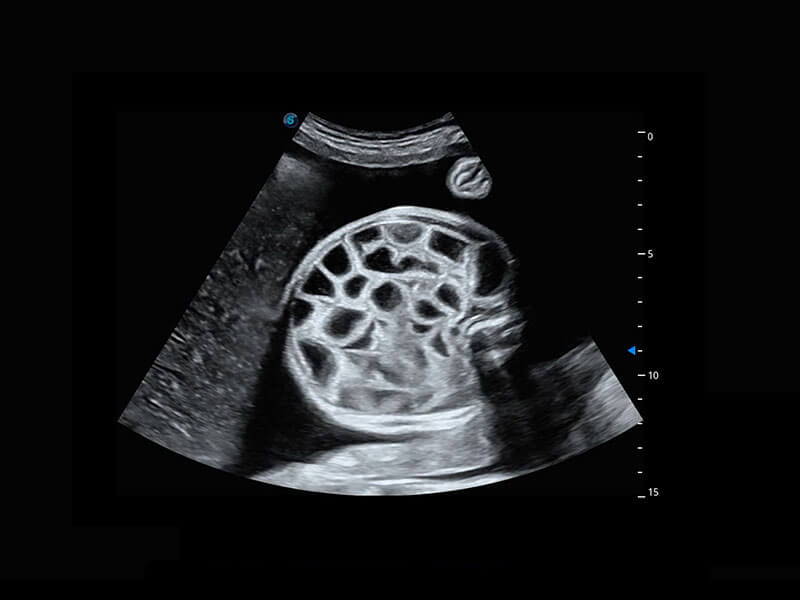

腔内妇科-卵巢